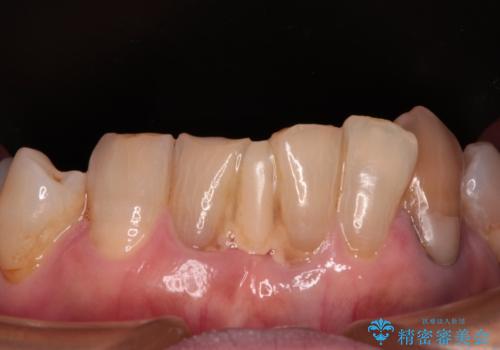

デコボコが強いため、ブリッジや残根となっている部分のスペースを利用して歯列を整え、変色や欠けている歯をオールセラミッククラウンによる補綴治療を行うこととしました。

歯肉移植などによる前歯部の歯肉ライン改善を提案しましたが、口を開けたときにほとんど見えないので気にならないとのことで、特に処置を行うことなく補綴治療を行いました。